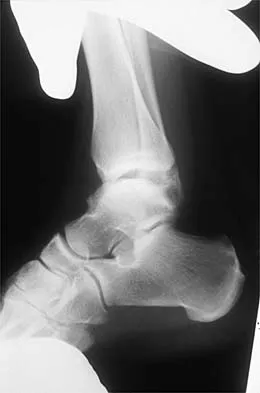

Question 67 High Yield

A 32-year-old laborer reports left ankle pain and deformity. History reveals that he sustained a left ankle fracture 2 years ago and was treated with closed reduction and casting. Radiographs are shown in Figures 25a through 25c. What is the most appropriate management?

Detailed Explanation

Corrective osteotomy of fibular malunions, with appropriate lengthening, even in the presence of early arthritis, has been shown to decrease ankle pain and increase stability. Reduction and bone grafting of the medial malleolar nonunion is also needed. There is no evidence supporting the use of intra-articular steroids or hyaluronic acid in the ankle joint. Lateral talar displacement of even 1 mm has been reproducibly shown to decrease tibiotalar contact by 40% to 42%, causing a predisposition to arthritis. Weber D, Friederich NF, Muller W: Lengthening osteotomy of the fibula for post-traumatic malunion: Indication, technique and results. Int Orthop 1998;22:149-152. Lloyd J, Elsayed S, Hariharan K, et al: Revisiting the concept of talar shift in ankle fractures. Foot Ankle Int 2006;27:793-796. Offierski CM, Graham JD, Hall JH, et al: Later revision of fibular malunion in ankle fractures. Clin Orthop Relat Res 1982;171:145-149.